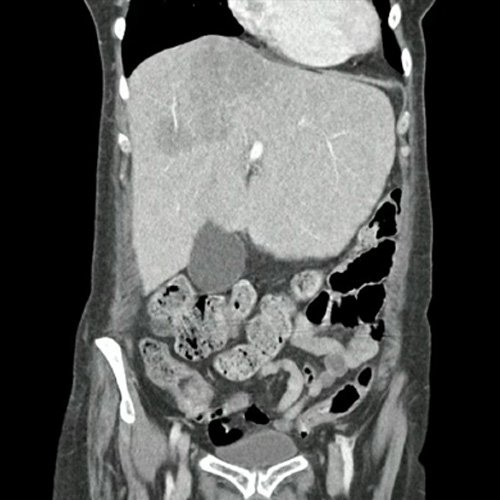

• TAC de abdomen y pelvis CC EV - informe preeliminar (Dia 30): En esta ocasión se observa hepatomegalia. Sus bordes son agudos. Continúa visualizándose de mayor tamaño, involucrando a casi la totalidad del segmento IV, una lesión nodular, de márgenes irregulares, hipodensa, ligeramente heterogénea, subcapsular, de bordes parcialmente definidos, Mide 9 cm CC x 6.5 cm DT x 5 cm AP (antes medía 5,3 cm CC x 4 cm DT x 3,7 cm AP). Actualmente se observa otra lesión nodular adyacente a la anterior descripta, en el segmento IVa/VIII, de similares características, que mide 3.5 cm DT x 3 cm AP, y otra en segmento IVa/II que mide 3 cm CC x 1.5 cm DT x 1 cm AP. Además se destacan otras dos lesiones, con similares características que las previas descriptas en segmento II que mide 19 mm DT x 15mm AP y en segmento VI que mide 14mm DT x 17mm AP. Hallazgos que podrían corresponder a secundarismo vs proceso infeccioso. Cotejar con datos clínicos de la paciente. Múltiples estructuras ganglionares retroperitoneales, pre y lateroórticas, hiliares hepáticas y esplénicas aumentadas en número y de tamaño, destacándose, en actual estudio,  una preaórtica derecha que mide 10 mm en su eje corto. En base pulmonar derecha se observan múltiples formaciones nodulares sólidas, irregulares, que realzan de manera heterogénea tras las administración de contraste E.V, como así también se observa otra de similares características en pulmón izquierdo en contacto con pericardio, la cual es la de mayor tamaño y mide 19 mm DT x 17mm AP. Hallazgos que obligan a descartar secundarismo pulmonar. Leve derrame pleural derecho. Hallazgos no visualizados en TC previa. Esplenomegalia que muestra densidad discretamente heterogénea, con algunas zonas de hiporrefuerzo de aspecto nodular. Trombos murales y calcificaciones parietales aortoiliacas. Aisladas formaciones diverticulares en colon sigmoides, sin cambios inflamatorios al momento del examen. Pequeña hernia inguinal epiploica izquierda, sin complicaciones agudas al momento del examen. Flebolitos pelvianos. Granuloma calcificado en TCS del glúteo izquierdo que mide 14mm. No se identifican alteraciones en las estructuras óseas visualizadas. Lesión osteoblásticas en cuerpo vertebral de L2.

Por presentar persistencia de dolor abdominal inespecífico, se solicita tomografía con contraste la cual informa hepatomegalia concordante con palpación abdominal (5 traveses de dedo por debajo del reborde costal), aumento de tamaño de lesión hepática previa y nuevas lesiones asociadas. En la tomografía de tórax se visualiza la presencia de nuevas imágenes nodulares sólidas, irregulares y heterogéneas distribuidas en ambos campos pulmonares.

TAC de abdomen y pelvis (Dia 30)